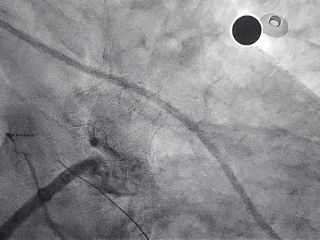

封堵器完全释放

右前斜

右肩位

左前斜位

肝位

多角度观察心包积液情况,无新增心包积液,同时封堵器稳定封堵心耳口部。